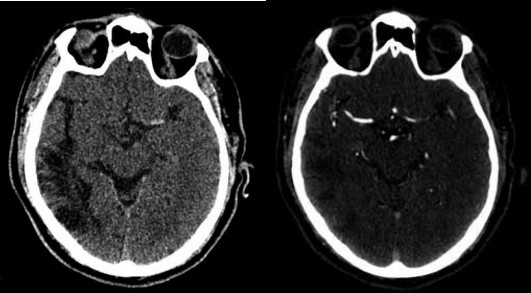

Considere o caso clínico a seguir para responder à questão.

Paciente do sexo masculino, de 65 anos, foi trazido ao pronto-socorro com início súbito de afasia e hemiplegia direita há 4 horas. No exame clínico, apresentado NIHSS de 20. A tomografia computadorizada (TC) de crânios realizada não mostrou sinais de hemorragia intracraniana, mas evidenciou hipodensidade corticossubcortical no território da artéria cerebral média esquerda, com classificação ASPECTS de 8.

Considerando o exposto, qual é a conduta imediata mais apropriada para esse caso?